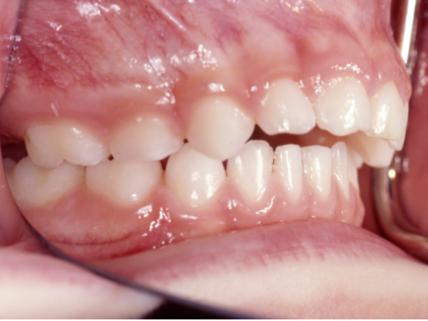

非营养性吮吸习惯可能与乳牙列和混合牙列的错牙合畸形患病率增加以及上前恒牙外伤的发生风险增加相关。可能会出现以下图片中的问题,包括前牙开牙合;后牙反牙合;深覆盖和上颌相对下颌过于前突的Ⅱ类错牙合。